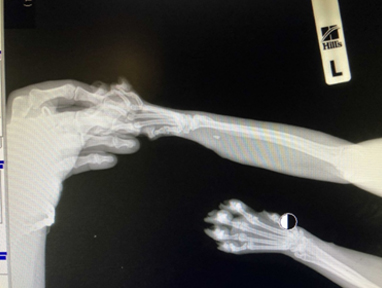

В ходе обследования было выполнено рентгенологическое исследование конечности, в результате выявлено, что в мягких тканях локализуется инородное тело (зуб). Как оказалось, кот был на даче, где и подрался со своим сородичем, который оставил в лапе нашего пациента данный «трофей».